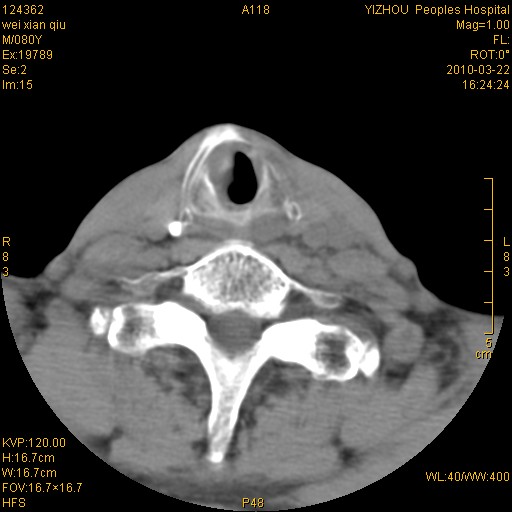

标题: CT25263:喉部占位?

男,80岁.声嘶三月余.

喉前庭右侧壁明显增厚,并见向内突出的软组织密度新生物,表面光滑,其后方软组织层次尚清晰,多考虑:喉部乳头状瘤!建议喉镜并病检!

右侧声们下区新生物